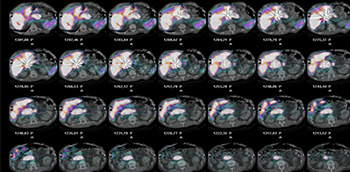

Radioembolización de las metástasis hepáticas

El hígado el tercer órgano en orden de afectación por las metástasis de tumores primarios originados en otras localizaciones (solo detrás de los ganglios linfáticos y el pulmón). Supone además la primera causa de muerte en pacientes afectados por metástasis y un...